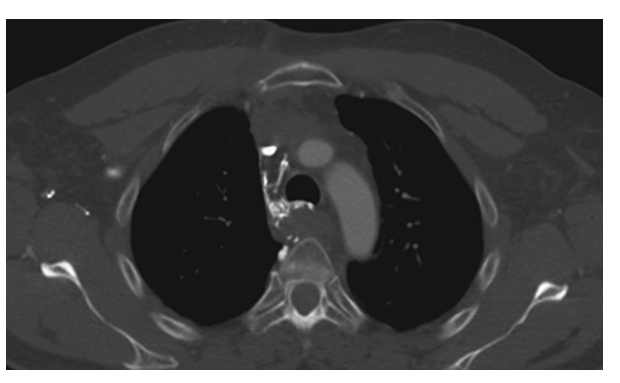

Histoplasmosis. Axial CECT shows two well-ground glass nodules in the right mid lung in a patient with histoplasmosis.